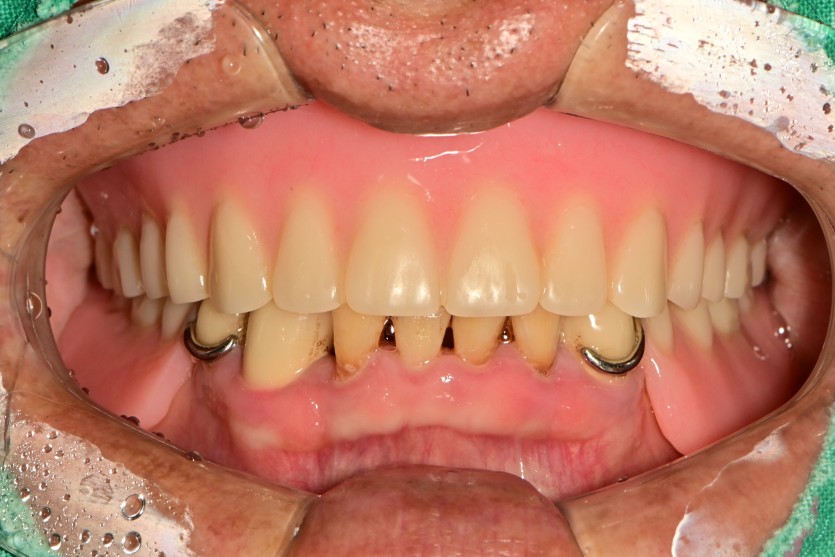

만 68세 상악 전체 임플란트 증례(하악 일부)

상악 전체 임플란트 증례입니다.(하악 일부)

15개의 임플란트로 완성하였습니다.